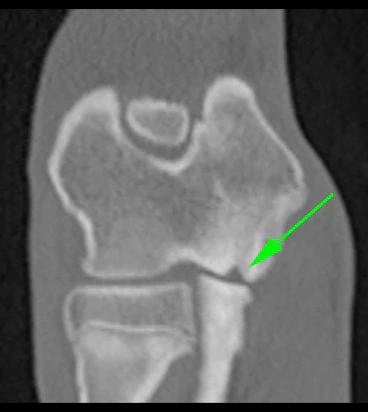

OCD anormal kıkırdak gelişimine bağlı bir hastalıktır. Çok hızlı büyüyen büyük ırk köpeklerde kıkırdak gelişimindeki aşırılık o bölgede oluşan düzensiz bir kıkırdak dokuya sebep olur ve eklemin uyumu kaybolabilir. Daha sonra bu fazladan üreyen kıkırdak doku parçalanabilir ve eklem yüzeyinde bir lezyon oluşur.

En belirgin belirtiler arasında topallama ve bölgedeki şişlik, sertlik ve sıcaklık vardır. Hasta oyun oynamak istemez, dirsek eklemine dokunulduğunda ağrılıdır. Bu tür durumlar başka dirsek hastalıklarından da kaynaklanabilir. Bu sebeple ayırıcı tanıyı koyabilmesi için alanında uzman bir veteriner ortopedi uzmanına köpeğinizi zaman geçirmeden götürmeniz gerekir. Teşhiste çabuk davranmak önelidir çünkü OCD’si olan her köpekte aynı anda osteoartrit gelişmeye başlar. Osteoartritin kesin bir tedavisi olmadığı için erken teşhis ile yönetilebilmesi daha uygun hale gelir.

OCD’nin teşhisi fiziki muayeneyi takiben röntgen çekimleri ile koyulabilir. Bazı durumlarda artroskopi de etkili bir teşhis yöntemidir.